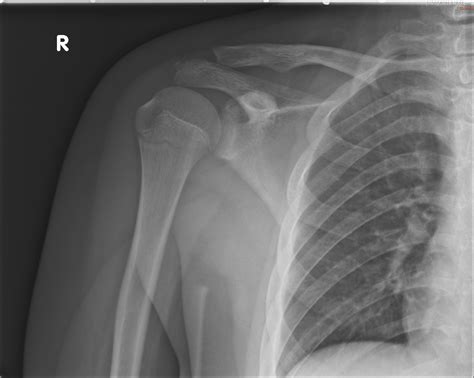

Interpreting a Shoulder Xray Normal

When a radiologist reviews a shoulder X-ray, they look for specific features that indicate a normal shoulder joint. These features include:

• Alignment of Bones: The humeral head should be properly aligned with the glenoid fossa of the scapula.

• Bone Density: The bones should have a uniform density without any areas of increased or decreased density.

• Joint Spaces: The joint spaces should be uniform and without any narrowing or irregularities.

• Soft Tissues: The soft tissues around the joint should appear normal without any swelling or abnormalities.

If all these features are present, the X-ray is considered Shoulder Xray Normal.

Common Findings in a Shoulder Xray Normal

A normal shoulder X-ray typically reveals the following:

• Humeral Head: The head of the humerus should be round and well-defined, sitting snugly in the glenoid fossa.

• Glenoid Fossa: The glenoid fossa should be smooth and without any erosions or irregularities.

• Acromioclavicular Joint: This joint should be well-aligned and without any signs of separation or dislocation.

• Clavicle: The clavicle should be intact and without any fractures or deformities.

• Soft Tissues: The soft tissues around the shoulder should appear normal, with no signs of swelling or inflammation.